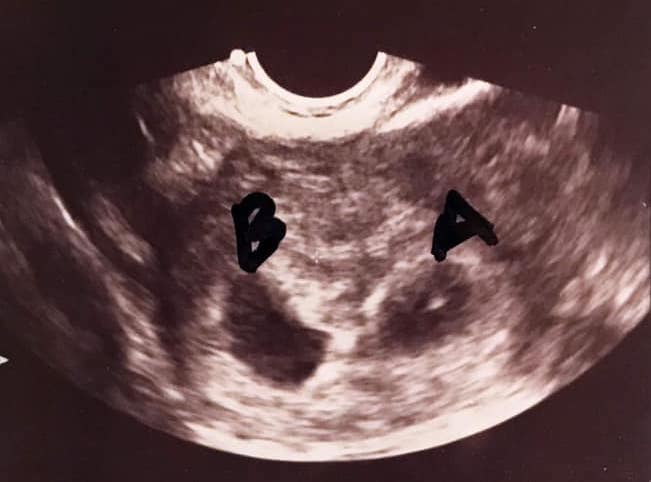

What Does an Ultrasound Look like at 6 Weeks Pregnant With Twins?

The earliest your doctor would likely order an ultrasound confirming twins would be 4 weeks pregnant. But unless you are going through fertility treatments, doing an ultrasound before 6 weeks isn’t very common, with the exception of complications. Women who are going through fertility treatments or have early complications may be able to have an early twin ultrasound at 4 or 5 weeks pregnant and find out they are pregnant with twins.

Yes! You’d need to have an ultrasound at 6 weeks to confirm a twin pregnancy. Your twin belly at 6 weeks may not look like much of a belly at all, so getting in to your doctor for an ultrasound is key to find out if you’re really having twins.